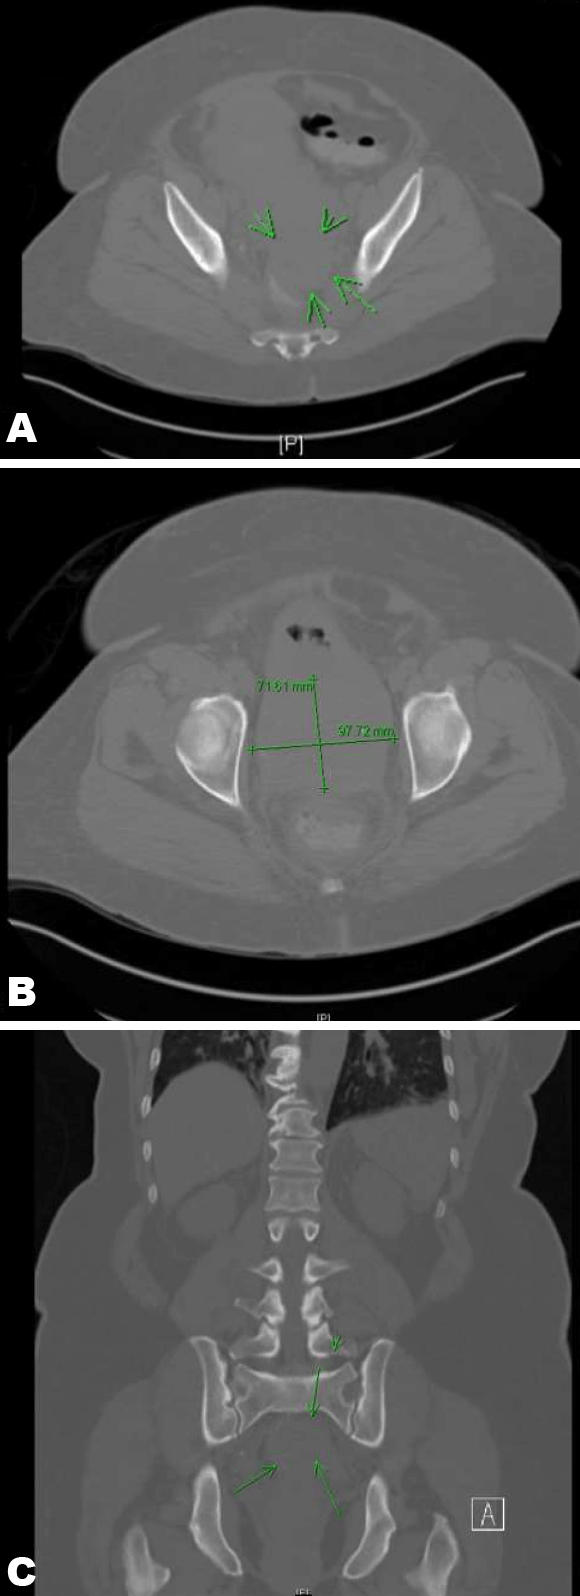

A 66-year-old postmenopausal woman presented with a one month history of fatigue, dysuria and hematuria. She received multiple courses of antibiotics as an outpatient without improvement. On admission labs, she was found to have a creatinine of 6.92 (baseline ~1.2). A retroperitoneal ultrasound was obtained and revealed bilateral moderate to severe hydronephrosis. A non-contrast CT abdomen and pelvis revealed a large ~7–9 cm mass involving the lower uterine segment/cervix displacing the rectosigmoid colon, likely representing the site of obstruction (Figure 1) (Figure 2) (Figure 3). An enlarged multi-fibroid uterus was also noted. There was no hepatosplenomegaly or adenopathy. On pelvic examination, a diffuse thickening was noted between the vagina and bladder. There was a firm mass wrapping around the cervix with thickening of the rectovaginal wall. She underwent further examination under anesthesia and multiple biopsies of the cervical mass were obtained. Patient also had bilateral percutaneous nephrostomy tubes placed to treat the obstruction.

Figure 1: (A–C) Computed tomography scan of abdomen and pelvis. A 7x9 cm mass involving the lower uterine segment and cervix.